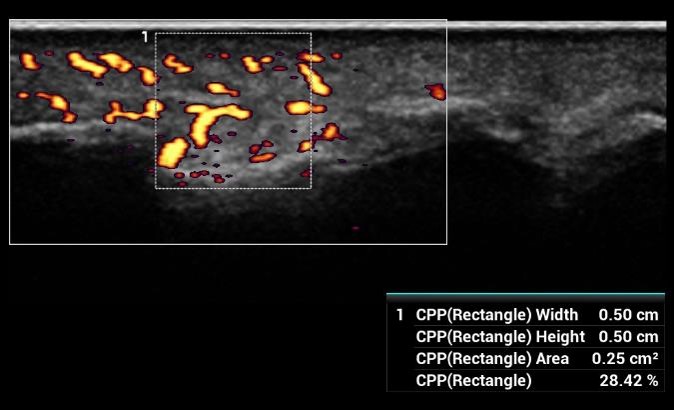

CPP - Percento farebných pixelov, výpočet percentuálneho podielu farebných pixelov v rámci definovanej oblasti záujmu

CPP: Vhodné na diagnostiku extrémne jemných prietokov (napr. reumatoidná artritída). Automatická štatistika percentuálneho podielu farebných pixelov v rámci vyšetrovanej oblasti.

CPP: Vhodné na diagnostiku extrémne jemných prietokov (napr. reumatoidná artritída). Automatická štatistika percentuálneho podielu farebných pixelov v rámci vyšetrovanej oblasti.

CPP: Vhodné na diagnostiku extrémne jemných prietokov (napr. reumatoidná artritída). Automatická štatistika percentuálneho podielu farebných pixelov v rámci vyšetrovanej oblasti.

CPP - Percento farebných pixelov, výpočet percentuálneho podielu farebných pixelov v rámci definovanej oblasti záujmu